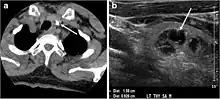

Fig. 4. A 45-year-old male patient presented with anterior mediastinal metastatic PTC lesions and occult primary on imaging. Histopathology examination of the resected thyroid gland revealed micro-foci of PTC; the largest, in the isthmus, measured 4 mm. a transverse greyscale ultrasound of the thyroid demonstrates homogeneous gland with normal echogenicity and size. No focal lesion or micro-calcifications. b Non-enhanced CT scan obtained as part of PET/CT examination shows a heterogeneous, large, relatively dense anterior mediastinal mass (white arrow) with peripheral calcification (arrowheads). Thyroid gland has normal CT appearance with no abnormal FDG uptake (not shown).[1]

Fig. 7. A 51-year-old female patient post total thyroidectomy for PTC with elevated thyroglobulin measurement. an Axial non-enhanced CT scan of the neck at the level of the thyroid bed demonstrates a well-defined, rounded, homogenously dense soft tissue situated between the trachea and left internal jugular vein (white arrow). b Transverse ultrasound image of the neck demonstrates a well-defined, homogeneous, hypoechoic soft tissue nodule measuring 6 mm (white arrow) with no detected micro-calcifications. Biopsy showed a predominantly residual normal thyroid tissue with micro-foci of PTC.[1]